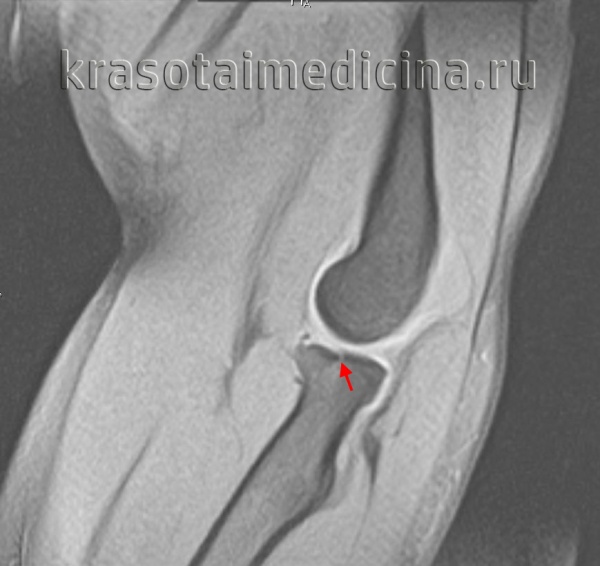

Интраоперационная оценка стабильности дистального радиоульнарного сочленения.